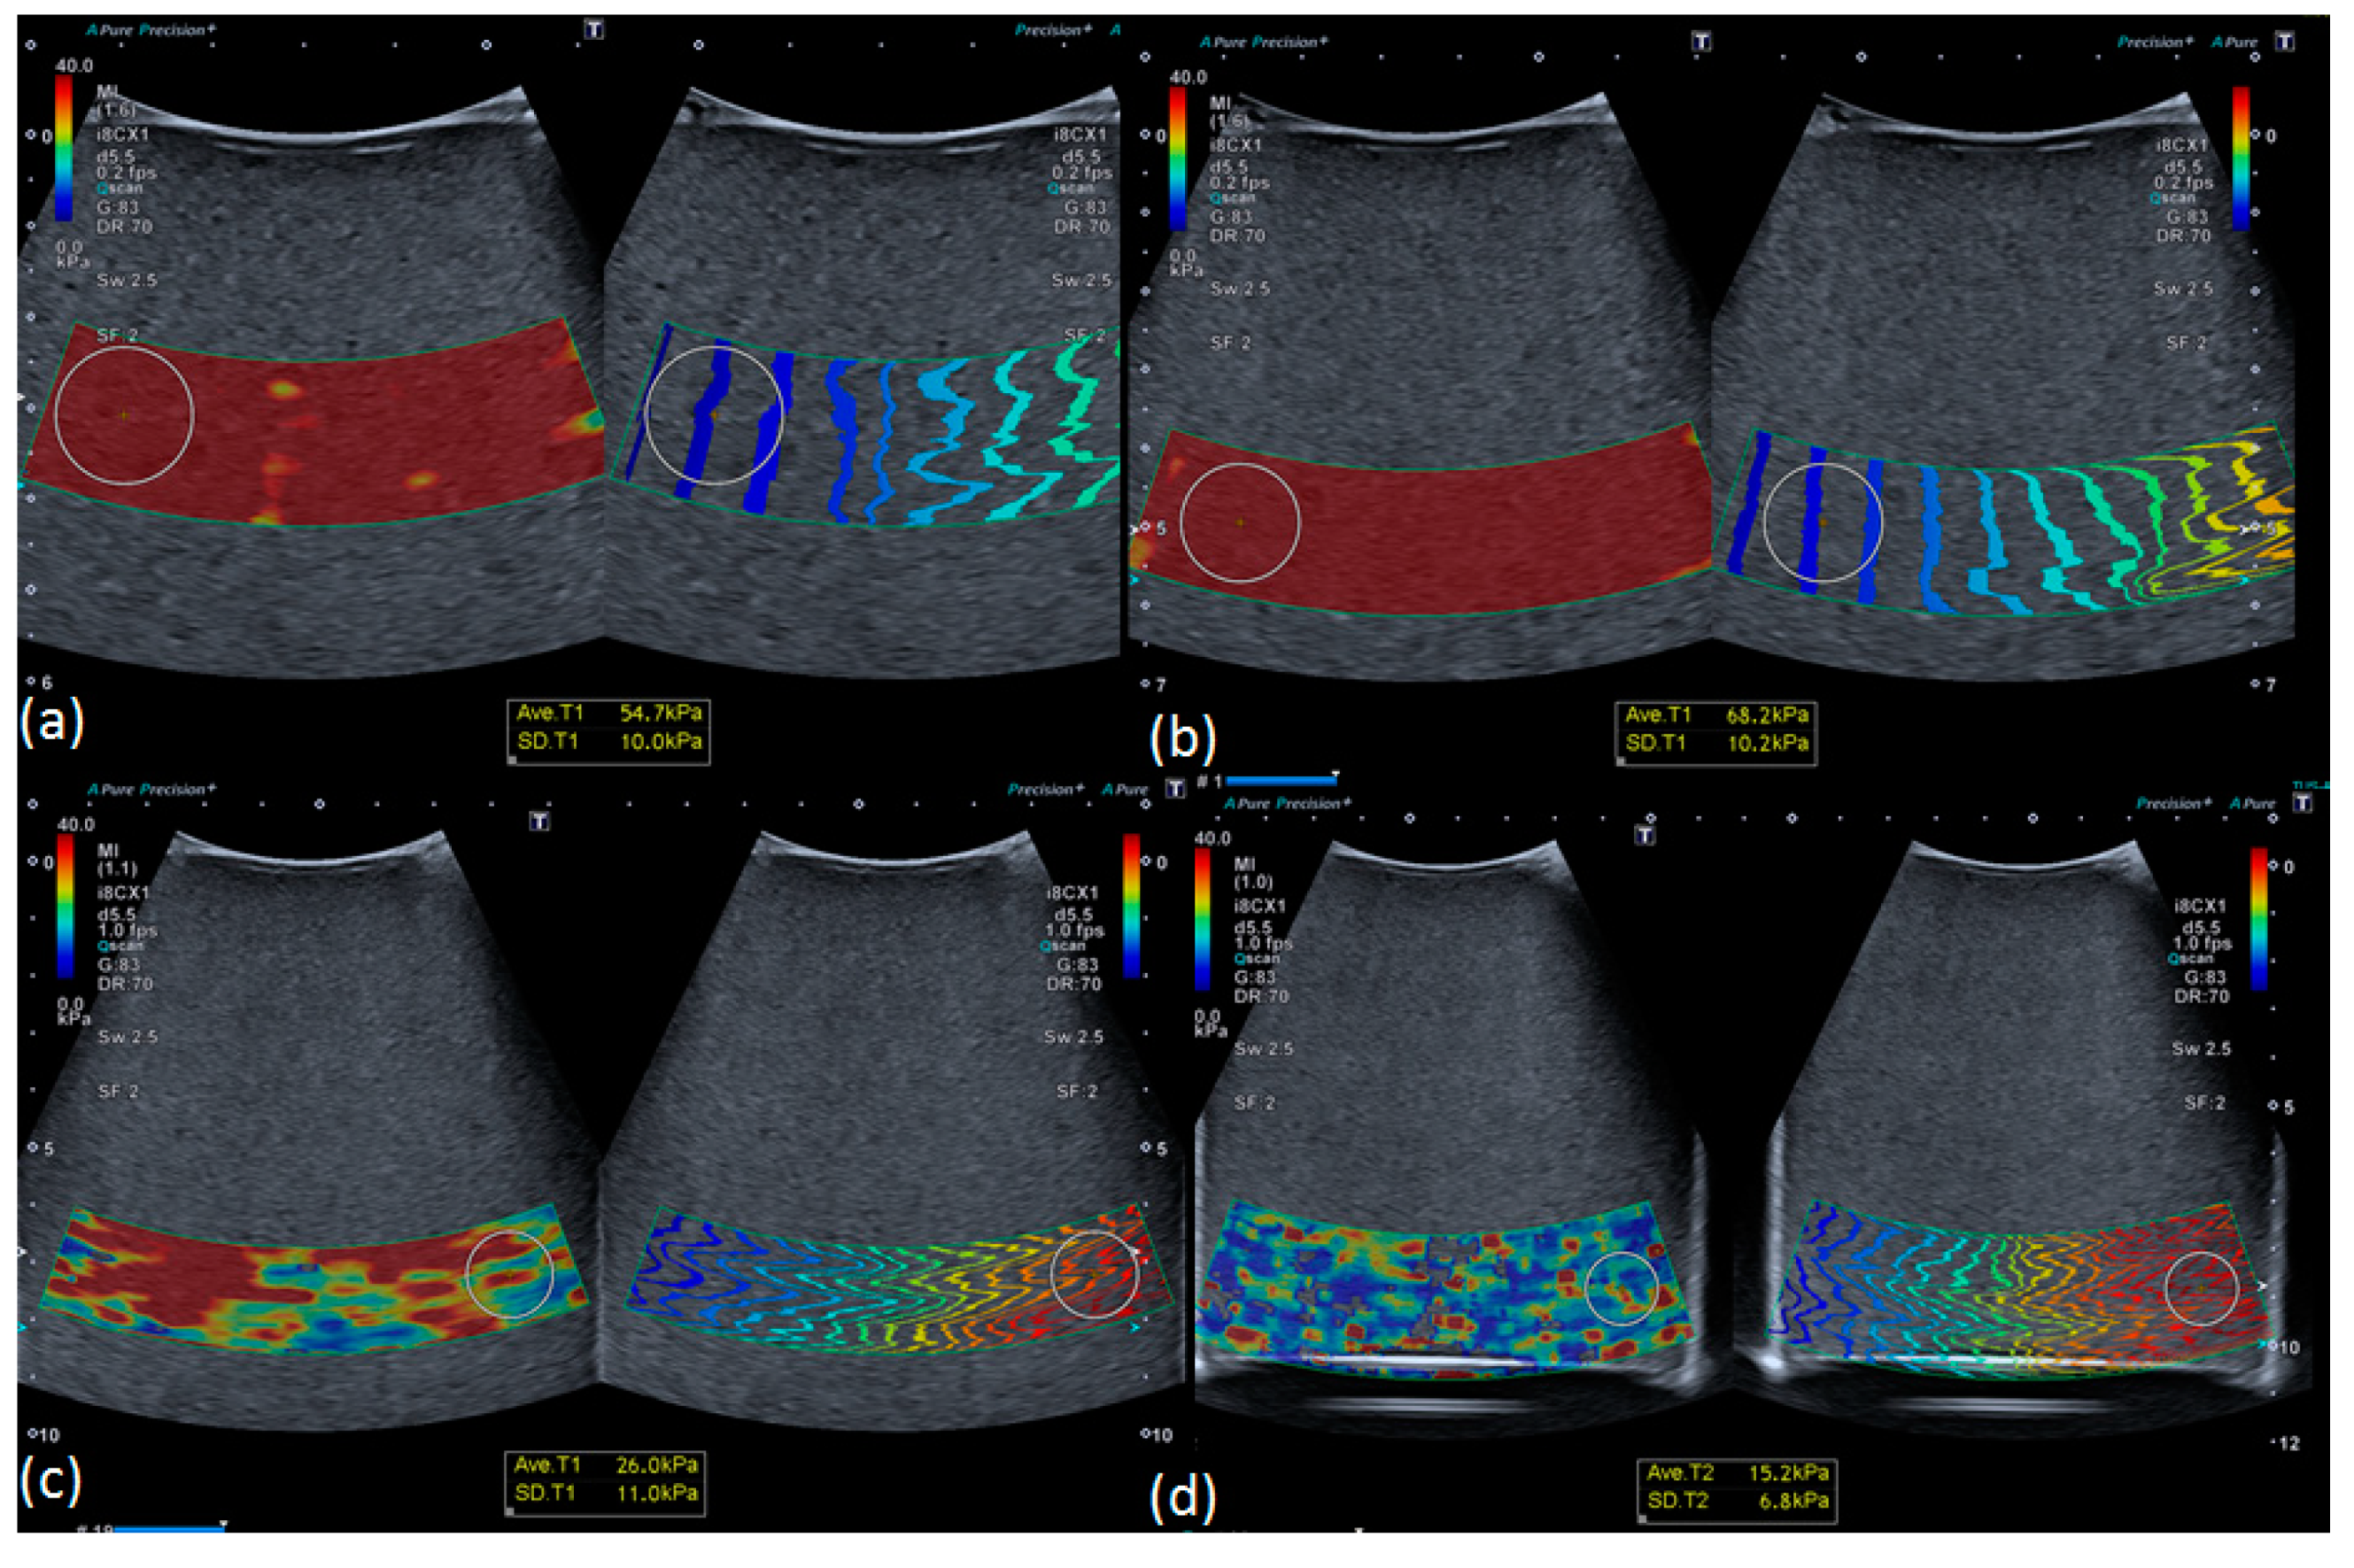

2.2. Ultrasonic-Based Elastography Phantoms

3.1. Robustness Evaluation Regarding Size and Type of Inclusions

3.2. Influence of Depth on Measured Stiffness